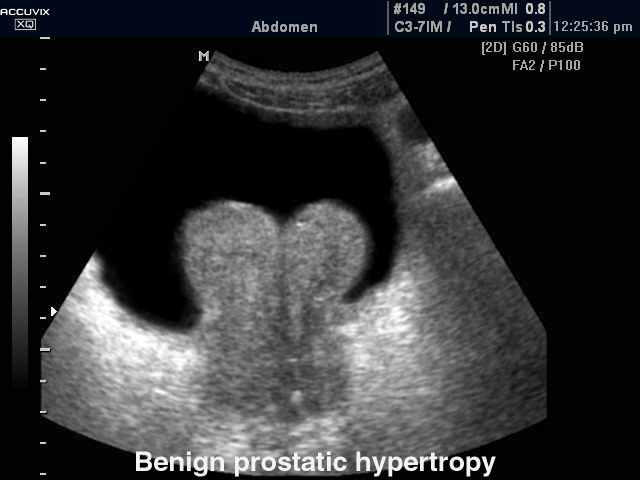

Доброкачественная гиперплазия предстательной железы.